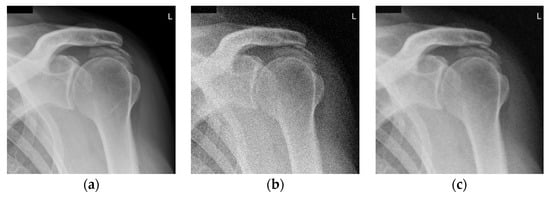

Shoulder X-ray images (with resolution 1024 × 1018) are presented in Figure 3. Namely, the noise-free image is given in Figure 3a. The noisy image is shown in Figure 3b (corrupted by additive white Gaussian noise (AWGN) the standard deviation of which is σ = 25). Figure 3c–e present images denoised using the RICI based method. Namely, Figure 3c is denoised using the quadrilateral regions, Figure 3d is denoised using the octagonal regions and Figure 3e is denoised using the hexadecagonal regions.

Figure 3.

Shoulder X-ray scan. (a) Original noise-free image; (b) Noisy image (AWGN with σ = 25); (c) Image denoised using the 2D LPA-RICI method (quadrilateral region, Г = 1.8, Rc = 0.8); (d) Image denoised using the 2D LPA-RICI method (octagonal region, Г = 1.8, Rc = 0.8); (e) Image denoised using the 2D LPA-RICI method (hexadecagonal region, Г = 1.8, Rc = 0.8); (f) Image denoised using Gaussian smoothing filters; (g) Image denoised using total variation denoising.

Denosing results, in terms of the PSNR, for the shoulder X-ray image are given in Table 1 (for various Г and Rc values). The first column gives regions (octagonal, octagonal and hexadecagonal, respectively). The second and the third column present parameter values for the 2D LPA-RICI denoising method. The fourth column presents the standard deviation of the AWGN. The fifth column provides the noisy image PSNR followed by the column giving the PSNR for image denoised using the proposed RICI based method. The last three columns of the Table 1 show the PSNRs of the images denoised using fixed size filtering (2D median filter), Gaussian smoothing filters and total variation denoising, respectively. For the Gaussian smoothing filtering a Matlab function imgaussfilt was used with standard deviation values chosen same as the standard deviations of the AWGN (σ = 20, 25 and 30). For the total variation denoising [12] Matlab function provided at the MathWorks was used with parameter λ chosen as λ = 0.2, λ = 0.25 and λ = 0.3 for the three tested AWGN levels (σ = 20, 25 and 30), respectively.

Table 2 gives PSNR improvements obtained using the 2D LPA-RICI method vs. noisy image and images denoised using the fixed size filtering, Gaussian smoothing filters and total variation method, respectively. As shown in Table 2, the proposed adaptive RICI based method outperforms the fixed size filters in all cases. Furthermore, it outperforms Gaussian smoothing filters and total variation denoising when quadrilateral and octagonal regions are used (hexadecagonal regions do not outperform Gaussian smoothing and total variation denoising methods).

Namely, the 2D LPA-RICI with quadrilateral regions increased the PSNR of the denoised image by up to 9.13 dB, with octagonal regions increased the PSNR by up to 10.50 dB and with hexadecagonal regions increased the PSNR by up to 4.69 dB (when compared to the noisy image). Also, the proposed 2D LPA-RICI method outperformed the fixed size 2D median filtering by up to 7.99 dB, the Gaussian smoothing filters by up to 6.08 dB and the total variation denoising by up to 4.35 dB for shoulder X-ray scan.